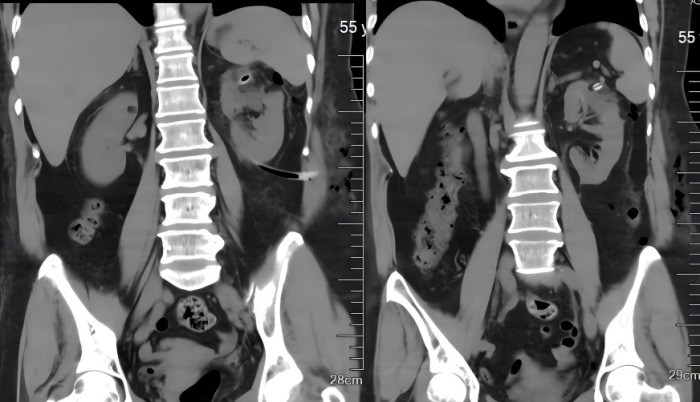

术后

患者,女,55岁,半年前在我院外科因急性阑尾炎住院手术治疗,术中发现左肾巨大囊肿(囊肿约10cm),当时因腹腔感染未能进一步手术处理。患者出院后自觉走路及轻量运动后出现左腰部酸胀,再次入住外科。经完善术前相关检查,排除手术禁忌症,与患者及其家属充分沟通后,决定由科室主任郭勇主刀为患者实施“后腹膜腹腔镜下左肾囊肿去顶减压术”。整个手术用时短,出血量少,术后第1天,患者即可正常下地活动、正常饮食,术后恢复良好于近日出院。